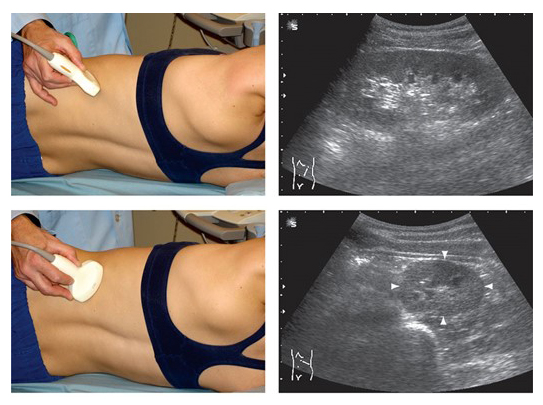

В-режим УЗИ

УЗИ почек проводится сначала в горизонтальном положении, а затем в вертикальном. Первоначальная позиция позволяет оценить аномалии развития и функционирование органа, в то время как стоя легче выявить дистопию.

Врач получает продольные, поперечные и косые эхографические срезы через переднюю стенку живота.

Сканирование в сагиттальной плоскости осуществляется, когда пациент лежит на животе.

Для получения изображения в фронтальной плоскости пациенту предлагают лечь на бок.

В этих режимах и плоскостях специалист анализирует все анатомические особенности структуры почек, включая:

- расположение почек и ворот органа;

- контуры;

- капсулу;

- наличие или отсутствие дольчатости;

- размеры почки: максимальная длина, ширина и толщина стенок;

- различие между корковым и медуллярным слоями;

- почечный синус.